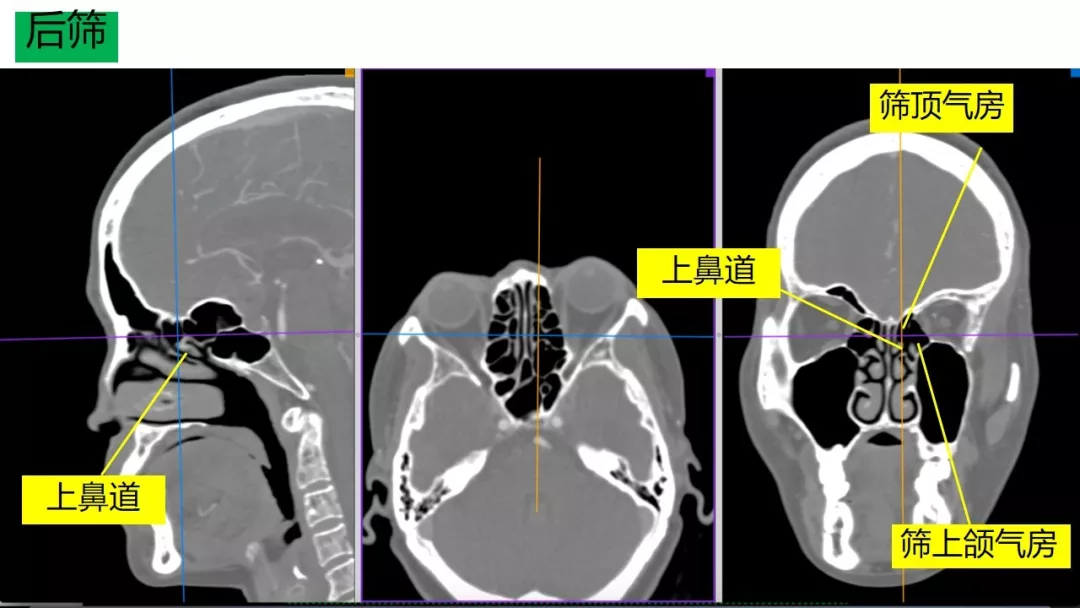

Osirix冠矢轴